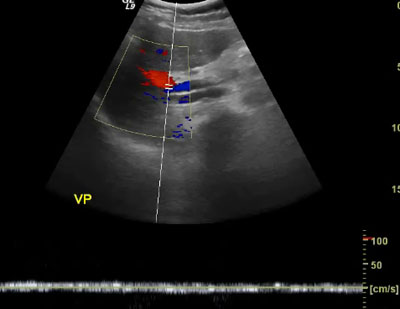

Echographie de la vessie (

). Bilan de colique néphrétique. On met en évidence un calcul (

) au niveau du méat urétéral avec dilatation de l’uretère (

) en amont.

L’échographie est l’examen de référence pour explorer la vessie. Normalement, avec cette technique l’uretère ne se voit pas. En cas de doute sur une pathologie urétérale, l’examen de référence sera l’uroscanner.